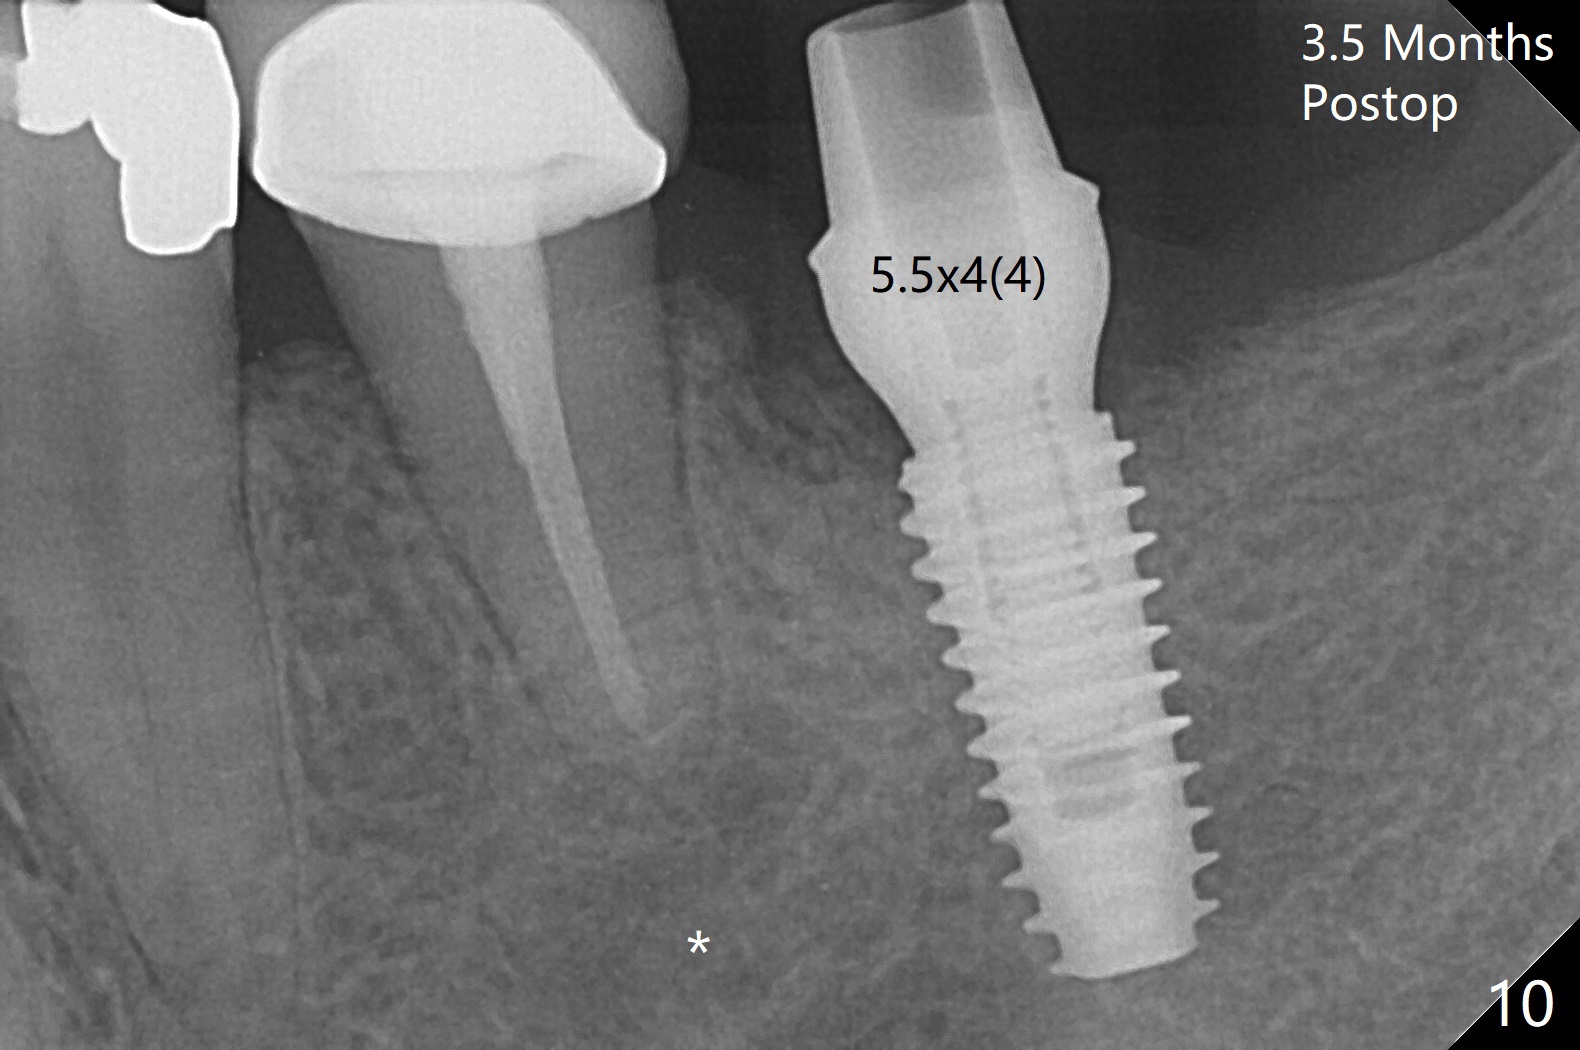

The tooth #20 develops lingual abscess when the patient returns for abutment placement 3.5 months postop (Fig.10 *).  Extraction and implant are apparently needed.